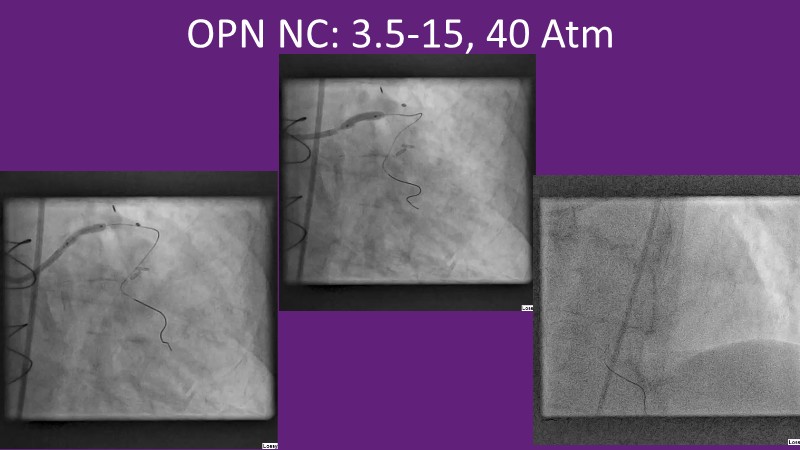

This EuroPCR 2025 session provides a comprehensive overview of drug-eluting balloons (DEBs) and their growing role in percutaneous coronary intervention (PCI). Gain a clear understanding of the clinical evidence and rationale supporting DEBs, including how these devices minimize metal implantation and effectively treat both standard and complex coronary lesions. The session highlights the mechanistic advantages of drug selection and sustained drug release technologies, with a focus on the SELUTION SLR DEB. Clinical updates include the LOVE-DEB study advocating a DEB-first approach in large vessel coronary artery disease, real-world performance data from the Malaysian registry, and practical case examples illustrating the transition to DEB-based PCI in clinical practice.